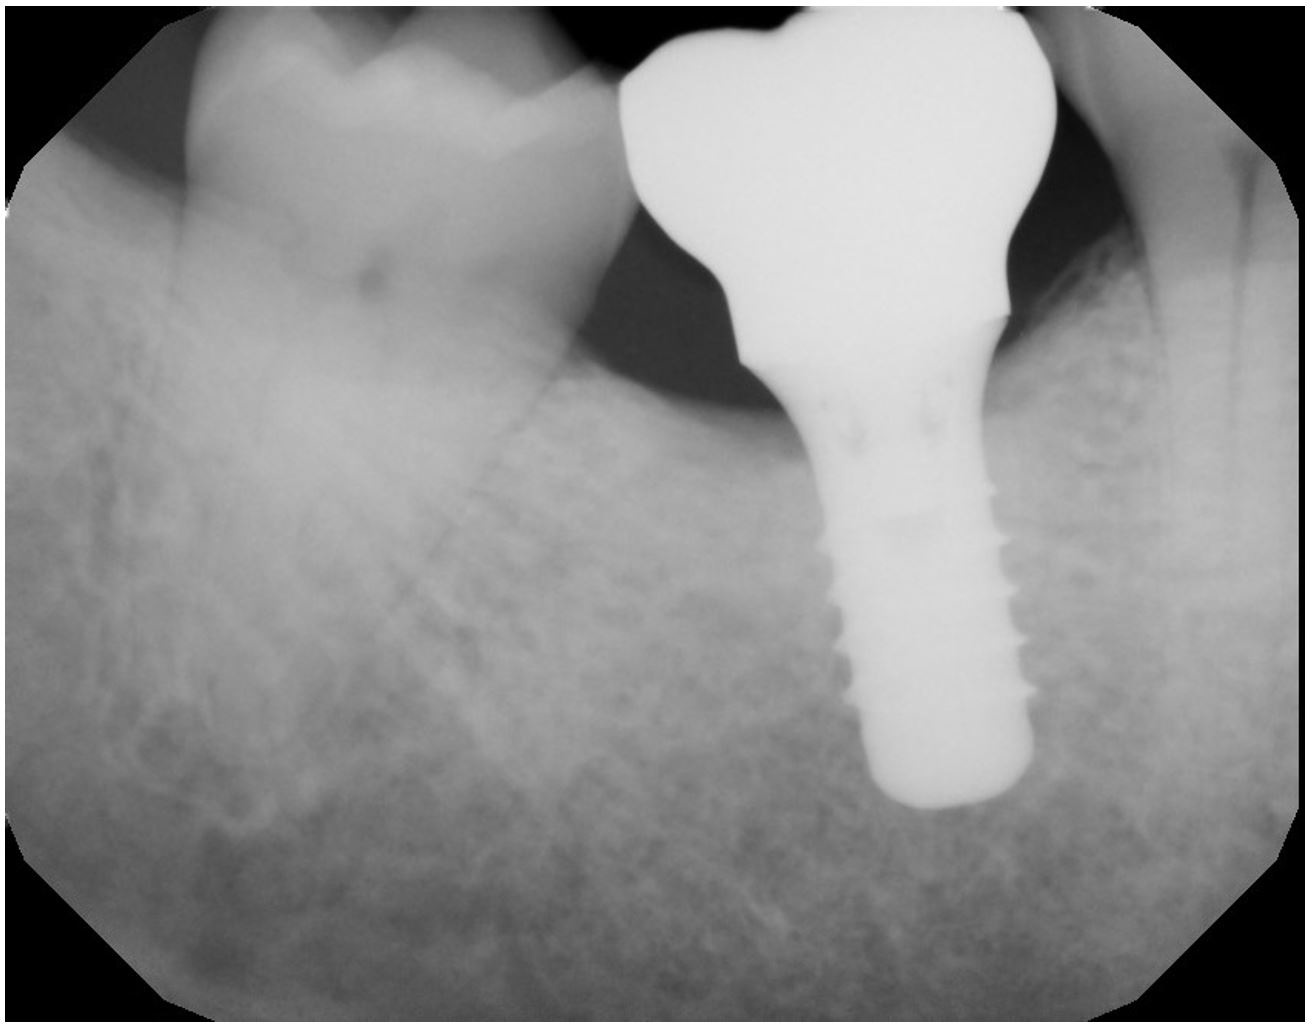

Laser for Periimplantitis

*Follow-up x-rays 9-12 months after treatment